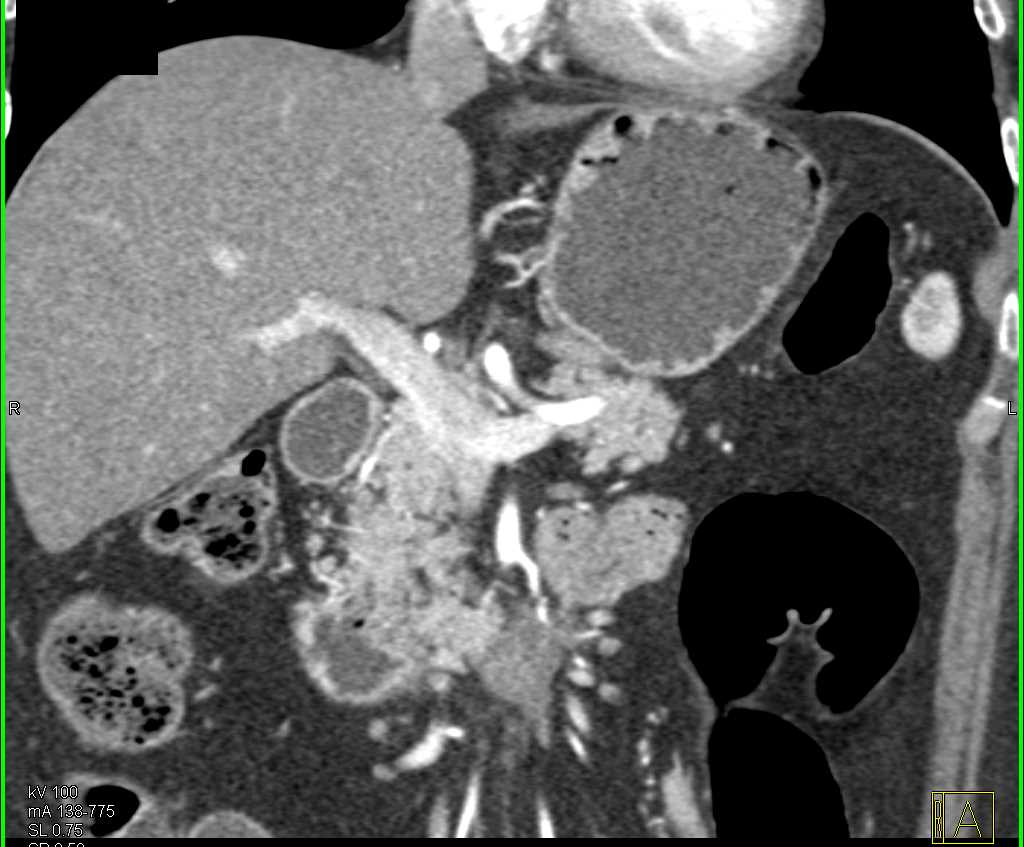

Duodenal Carcinoma with Obstruction